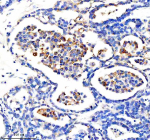

Immunohistochemical staining of CYP2W1 using anti-CYP2W1 antibody. CYP2W1 was detected in a paraffin-embedded section of human breast cancer tissue. Heat mediated antigen retrieval was performed in EDTA buffer (pH 8.0, epitope retrieval solution). The tissue section was blocked with 10% goat serum. The tissue section was then incubated with 2 ug/ml rabbit anti-CYP2W1 antibody overnight at 4oC. Peroxidase Conjugated Goat Anti-rabbit IgG was used as secondary antibody and incubated for 30 minutes at 37oC. The tissue section was developed using an HRP secondary and DAB substrate.